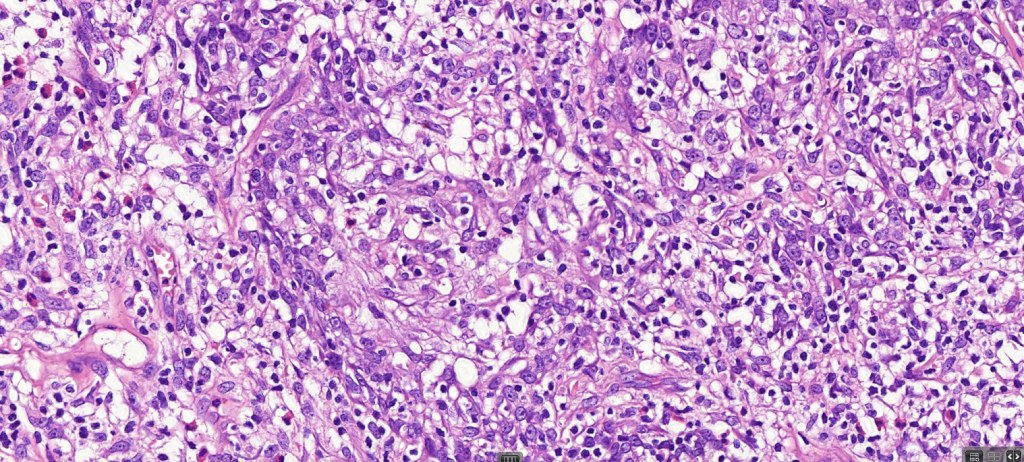

Histological features

•Follicular infiltration by atypical lymphocytes & Sézary cells

•Eosinophils sometimes conspicuous (eosinophilic folliculitis-like appearance)

•Granulomatous inflammation secondary to follicular destruction

•Large cell transformation occasionally present